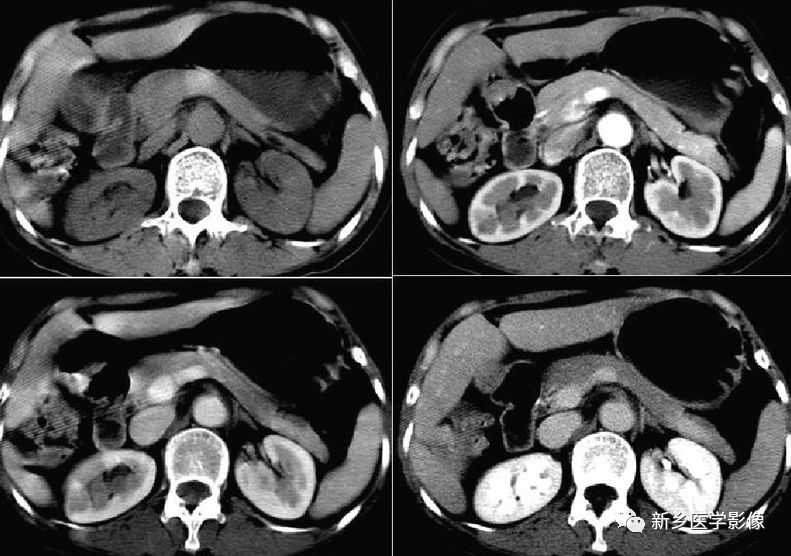

5肝副叶:

肝右叶后下方舌状突出,逐渐变小又突然变大,密度与肝实质相近,与肝脏相连。增强扫描与肝实质同步强化,特征性表现:正常肝脏内血管进入其内。鉴别诊断:肿瘤病变。